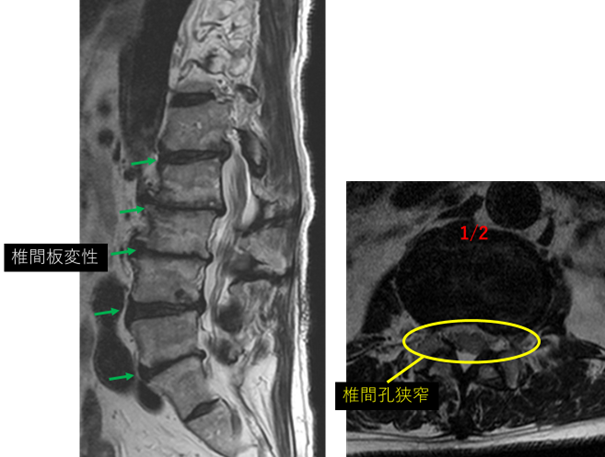

画像及び所見について

L1/2: 変性、左ヘルニア、左椎間孔狭窄、終板変性

L2/3: 変性、膨隆、減高、右椎間孔狭窄、終板変性

L3/4: 変性、膨隆、減高、右椎間孔狭窄、終板変性

L4/5: 変性、左ヘルニア、左椎間孔狭窄、終板変性

L5/S: 変性、膨隆、左椎間孔狭窄、終板変性

以上の事が画像上認められます。

L1/2、2/3、3/4、4/5、5/S に

椎間板変性、椎間板ヘルニア、椎間孔狭窄症、終板変性 を認め、主症状の原因の可能性が高い。